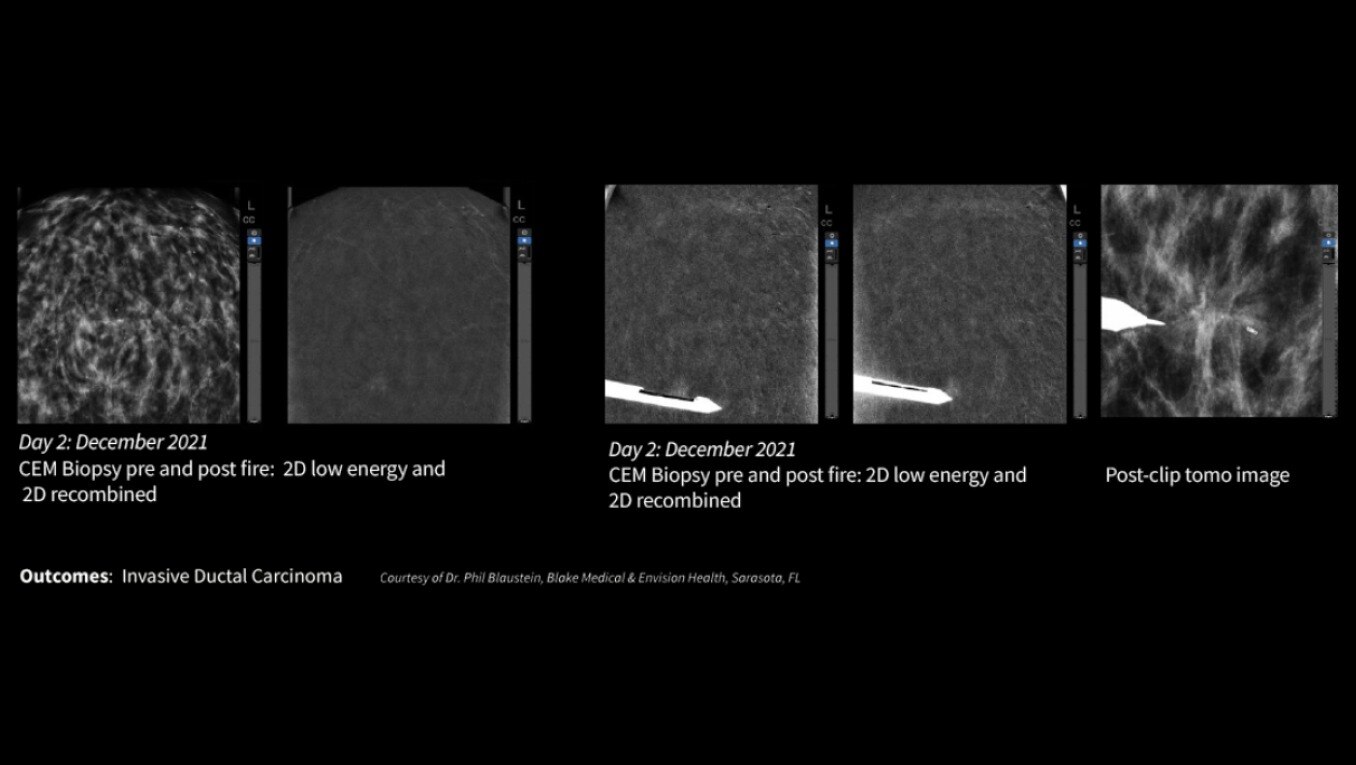

With over a decade of contrast mammography leadership worldwide, GE HealthCare’s contrast enhancing mammography (CEM) is a game changer in breast diagnostic imaging and biopsy care.

GE HealthCare pioneered this technology in 2010 and is associated with over 200 publications that demonstrate its clinical performance. GE HealthCare’s CEM combines the morphologic and density information similar to a conventional mammogram and the functional vascular information of a breast MRI1. It presents an opportunity to create and implement a more streamlined workflow to help diagnosis breast cancer early. In addition to increasing patient access, our CEM offering boasts high levels of sensitivity and specificity, allowing for the detection of lesions that would otherwise go undetected2,3,4. To ensure your practice can fully leverage the combined power of GE HealthCare contrast mammography solutions, we introduce Pristina Bright our comprehensive CEM package with complete support, from training to service, for your successful implementation.